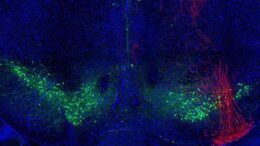

Parkinson’s disease

Novel Parkinson’s Procedure Pumps Up NSUH

By GREGORY ZELLER // They’re dancing in the aisles, literally, at North Shore University Hospital, thanks to a revolutionary treatment for Parkinson’s disease. Surgeons at the Manhasset hospital, part of…